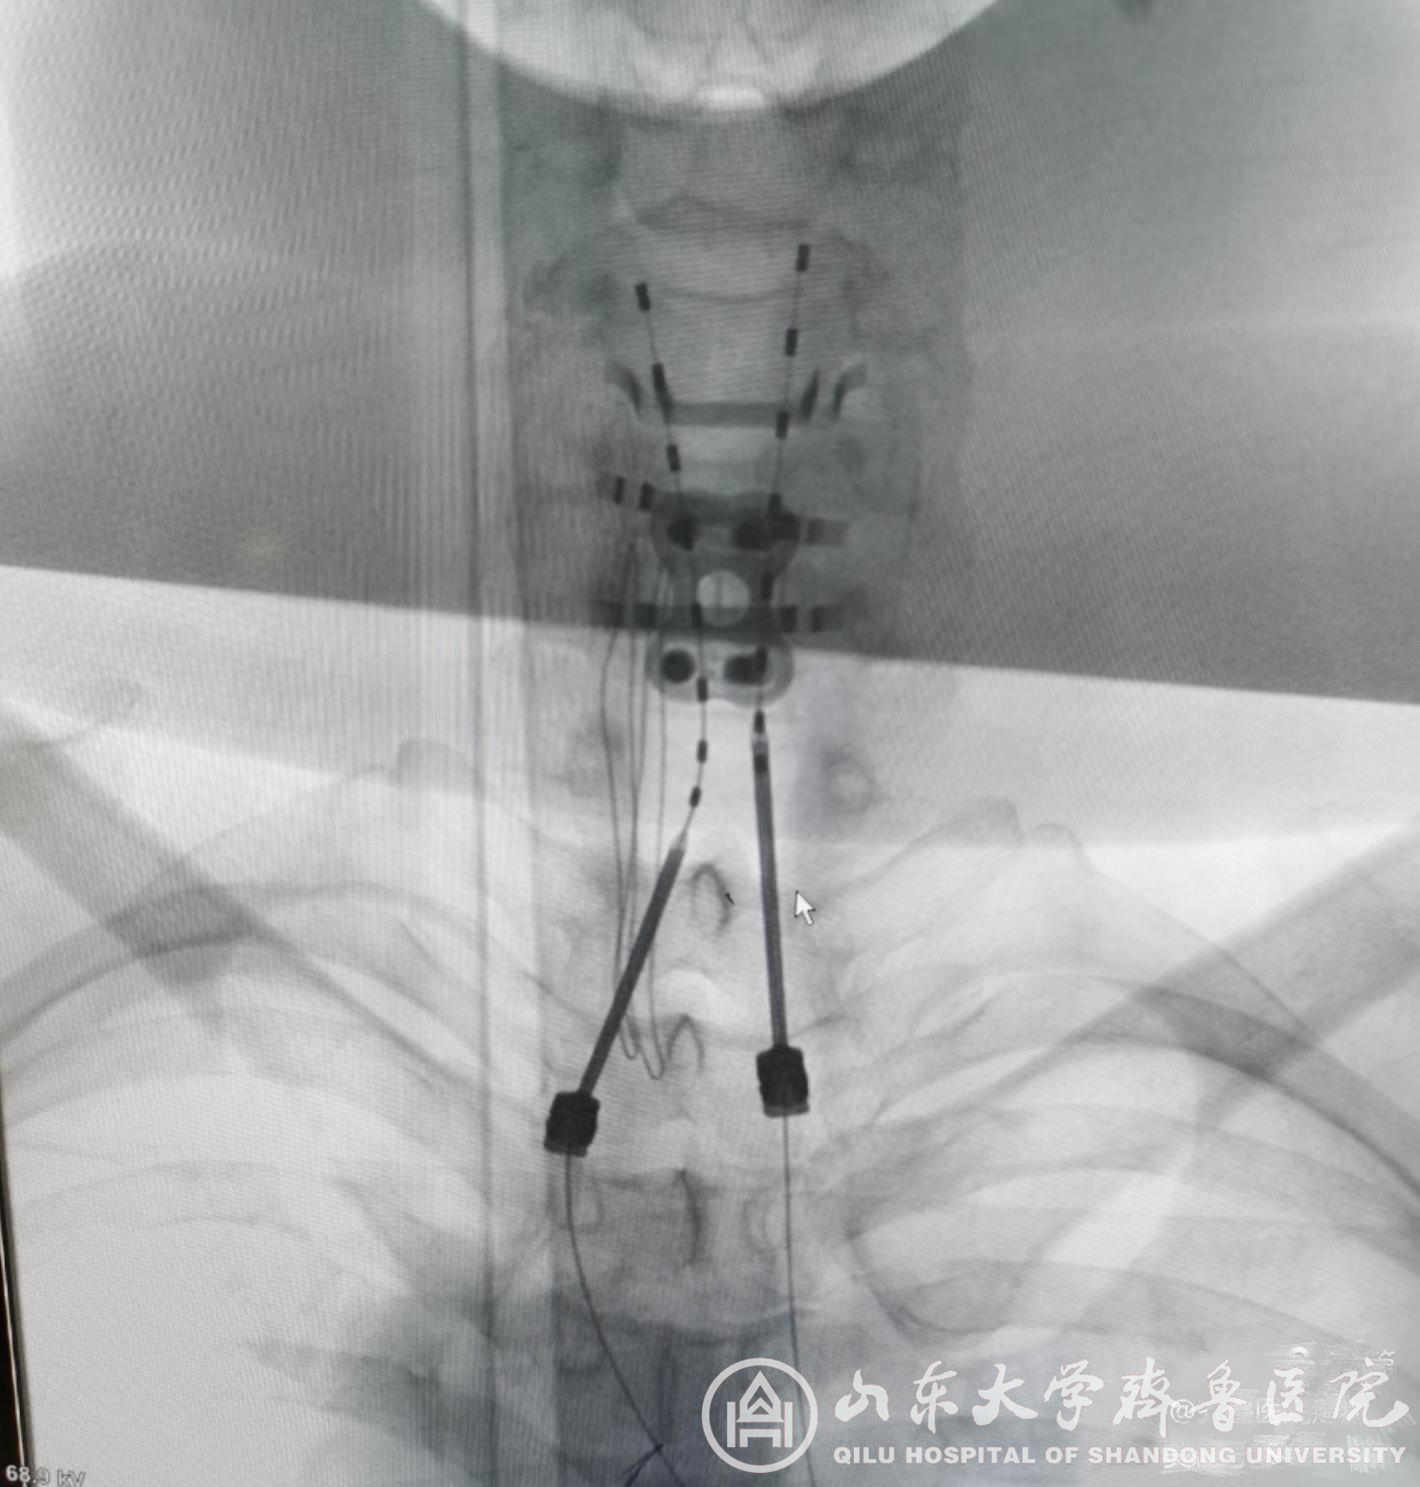

病例2患者中年男性,46岁,因“四肢及颈胸背部疼痛2年11个月”以“颈髓损伤后顽固性疼痛;截瘫”收入院。入院VAS评分9-10分。患者应用“普瑞巴林、氨酚羟考酮、曲马多、哌替啶”等止痛药物效果差。术前评估后,患者在局麻下行脊髓电刺激器植入术,植入双侧针状电极及临时刺激器。术中开机程控,患者感疼痛减轻,VAS评分2分,术后未再应用针剂镇痛,口服药物减量,经程控调整,VAS评分稳定至1-3分。4天后行永久脊髓电刺激器植入术,患者VAS评分稳定于1-2分,未出现术后不良反应及并发症。

图2.颈髓损伤后顽固性疼痛患者术中穿刺植入针状电极